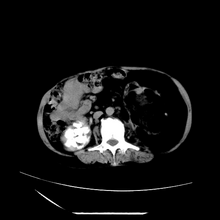

女性,41岁,发现左腹部包块3年,现行ct检查,检查前做过静脉肾盂造影。

左侧低密度区是脂肪密度,中间可见条索状软组织样密度影,现主要想知道左肾前下缘圆形软组织样密度影,内见低密度水样密度影,这是什么?

脾脏增大,左肾后方脂肪增多,脊柱前方脂肪增多,左肾窦脂肪增多,左肾变形,双肾积水以左侧为著,左肾内侧及上方见环形软组织肿物影,内部低密度区,考虑1盆腹腔/腹膜后及左肾窦脂肪增多症2左肾内侧病灶可能为左肾上腺病灶,可能为脂肪增多的原凶

1)考虑左肾替代性脂肪瘤病;不排除左肾错构瘤。2)双肾积水。

肾窦脂肪瘤病及肾替代性脂肪瘤病被认为是脂肪增殖程度不同的一种疾病。正常情况下肾窦内有少量脂肪组织充填,在某种情况下肾实质会发生萎缩,而以肾窦、肾门为中心脂肪或(和)纤维组织可出现增殖,当增殖局限在肾窦、肾门区时称为肾窦脂肪瘤,若同时部分或全部取代了萎缩破坏的肾实质时称为肾替代性脂肪瘤病。

发病机理有2种学说,大部分人认为是由于某些具有破坏性的肾脏疾病,如肾结石并感染、肾结核等造成肾破坏、萎缩,继发了大量的脂肪组织增殖;另一部分则认为肾脏慢性炎症可刺激脂肪组织的增殖,肾萎缩是继发的。

ct典型表现为以肾窦肾门为中心大量弥漫性脂肪积聚,鹿角状结石及萎缩的肾实质。合并肾周感染时,肾轮廓不清,周围有粘连性改变。

诊断主要需与含脂肪的肾肿瘤加以区别,如血管平滑肌脂肪瘤、脂肪肉瘤、脂肪瘤

诊断rsl的必备条件是肾窦、肾门的脂肪组织增生和肾实质的萎缩,而且本例因为ivp后扫描不好判断有无肾结石但可能性较小;另外,占位效应显著,脾后缘都受压了,肾门以下肾实质残缺,支持肾脏错构瘤.